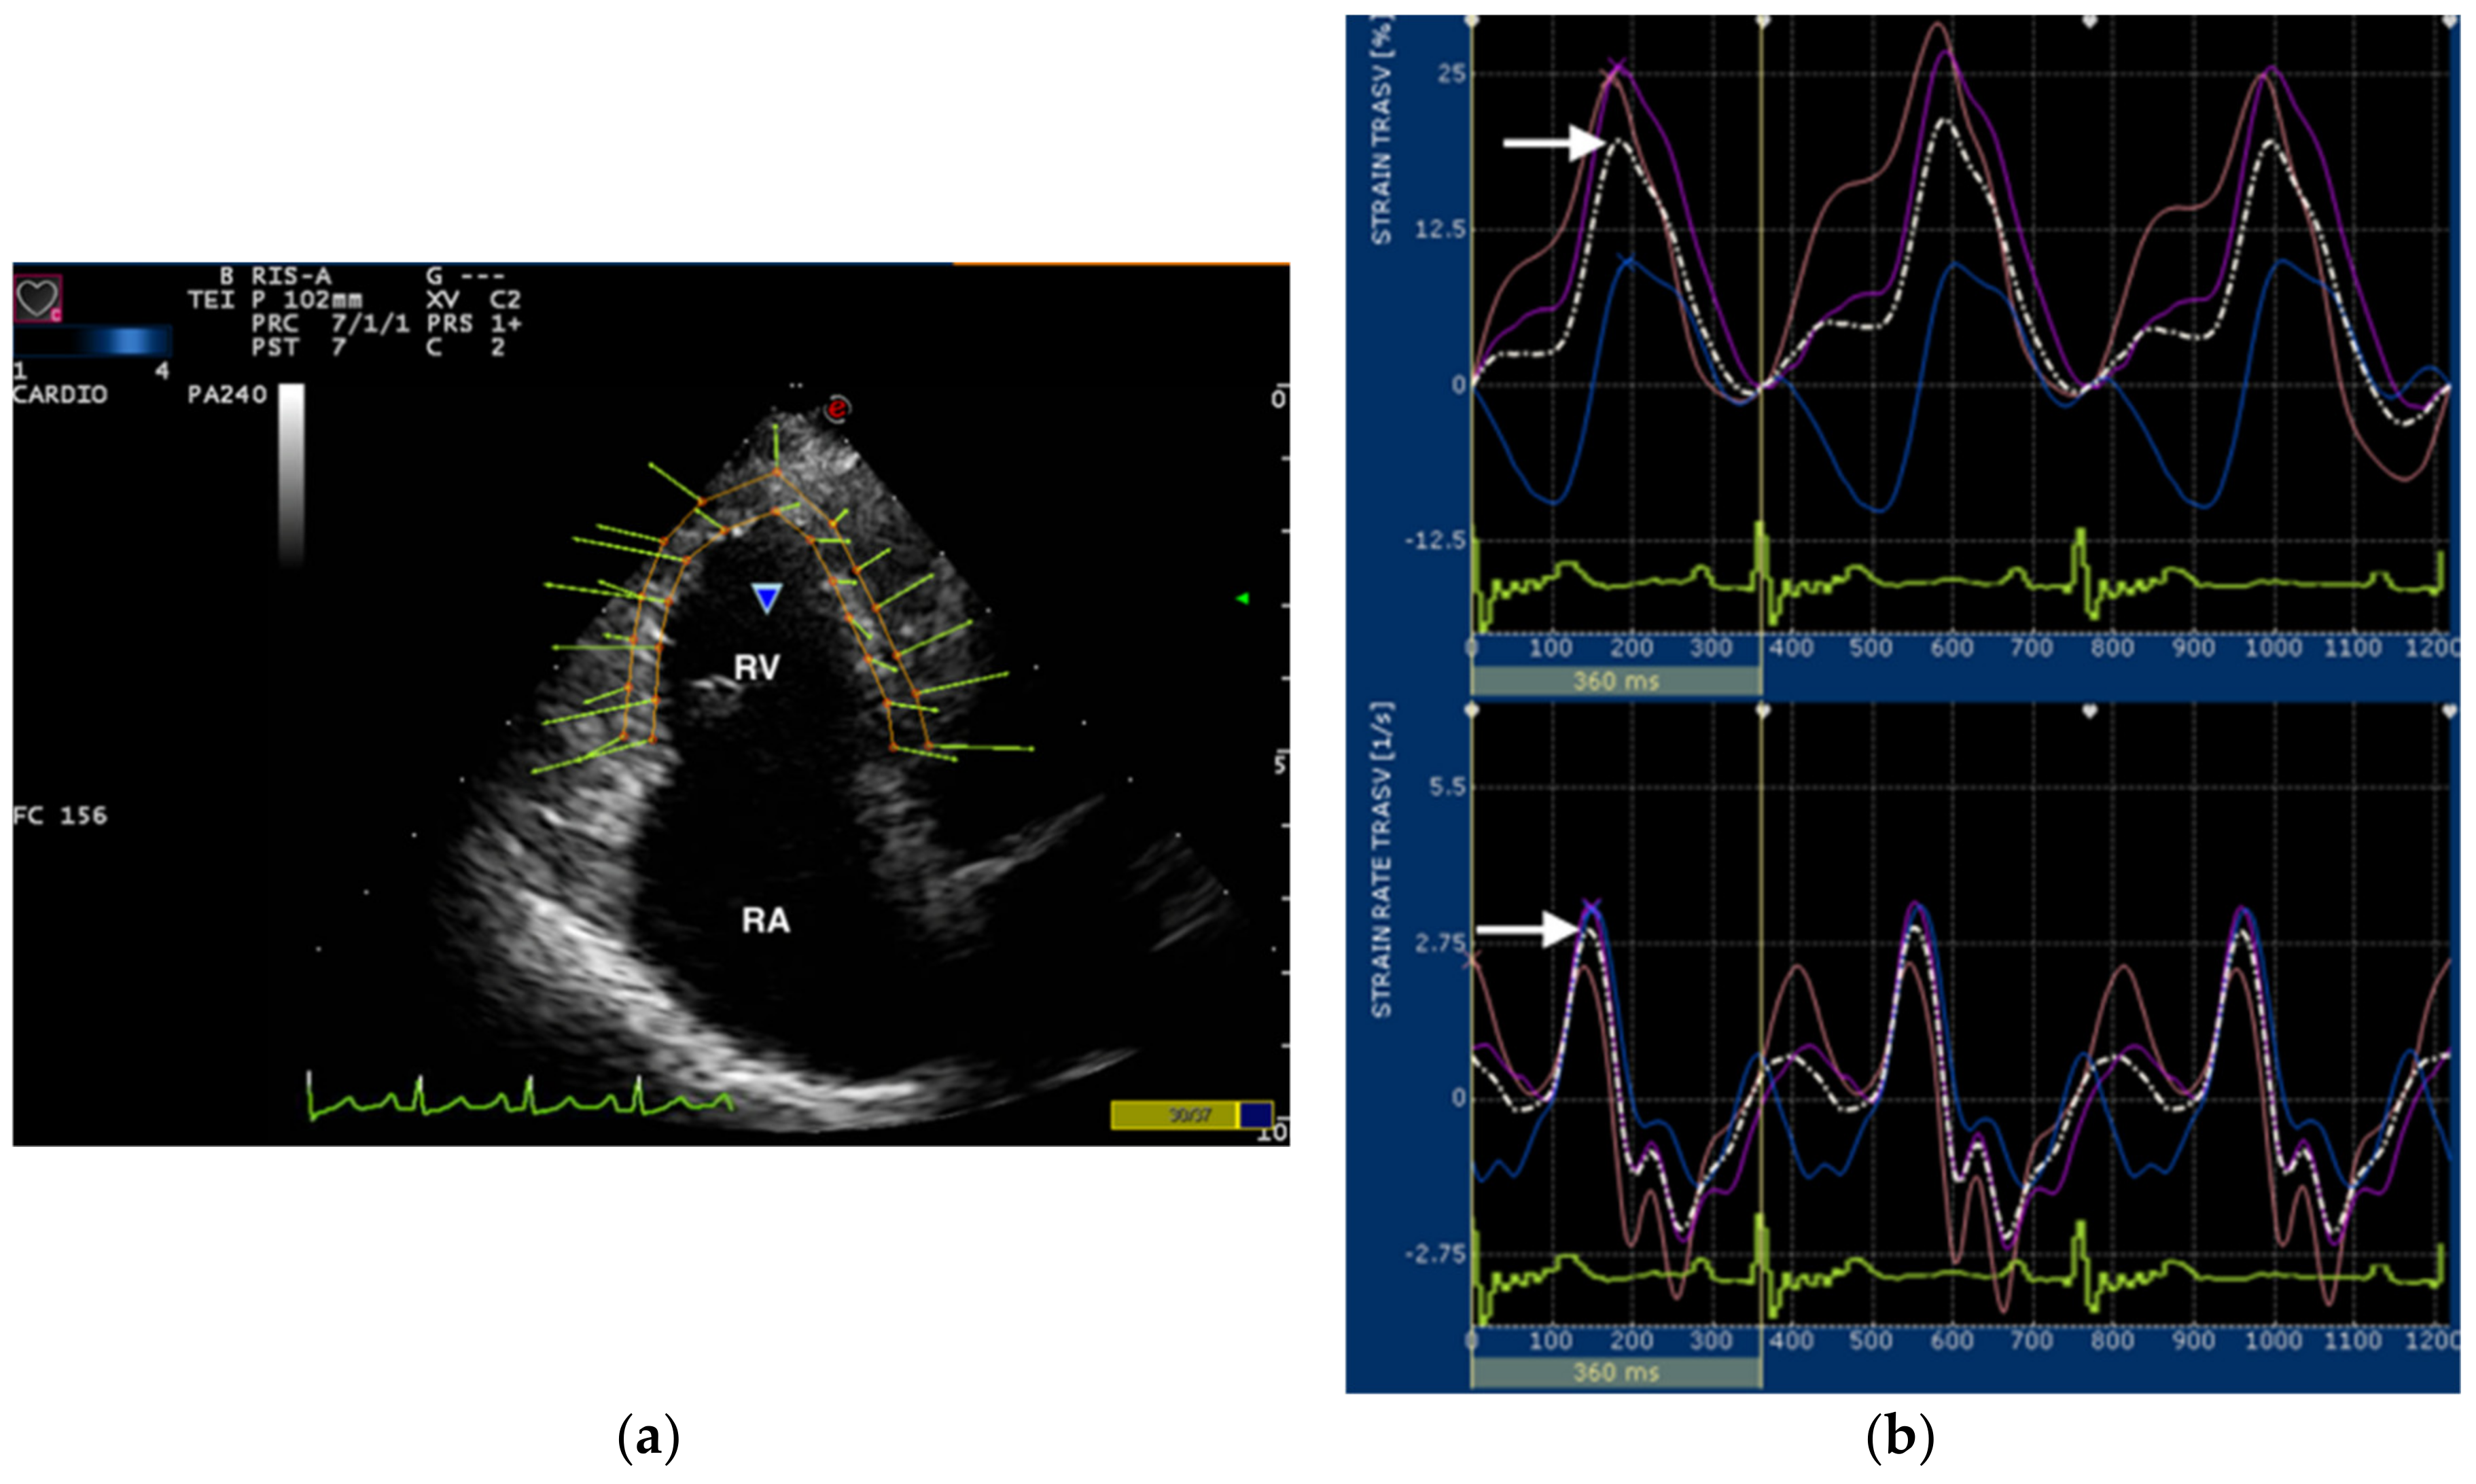

2.2. Speckle Tracking Echocardiography

| TR velocity (m/Section) Transverse RV Strain (%) Transverse RV Strain rate (1/s) | – 34.2 (20.5–71.1) 4.2 (1.9–6.0) | 3.7 (3.1–6.2) 35.7 (10.9–56.0) 4.6 (1.7–9.4) |